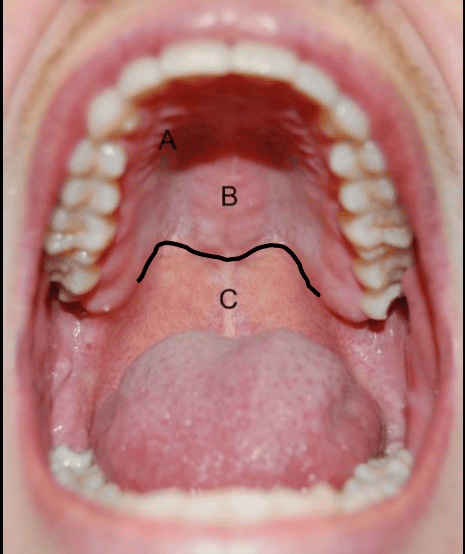

It may be due to the bleeding disorders or excess pressure found on the blood capillaries. Possible causes and medical suggestions. I have tiny bumps on the inside of my mouth. A bump can form on the roof of the mouth due to many conditions, including canker sores, mucoceles, torus palatinus, and oral candidiasis. Is it smooth or is there a bump? A bump on the roof of the mouth can be worrisome, especially if it does not go away quickly. Painful bumps on roof of mouth. 500 x 313 jpeg 20 кб.

Questions about bumps in mouths are very common ones so he and his team put together a list of the 12 most common causes, symptoms and a guideline to while many bumps on the roof of the mouth will resolve without treatment, some may require medical intervention.

In such cases, there is some bumps on the roof of the mouth like mucoceles go away without any treatment. Noticed semi hard bump on roof of mouth hard palate 6 days ago, about bb sized. Most causes of a bump on this part of the body are easily. A bump on roof of mouth that has been around for a long time may point to oral cancer. This article will cover the most common causes of a hard bump on the roof of your mouth. Having a bump on the roof of your mouth is not particularly uncommon.you have probably had them on your throat, lips, or tongue. Bumps and ulcers that appear on the roof of the mouth are not uncommon. They can also be either hard lumps or soft sores. Tiny bumps cream, tiny bumps on skin, tiny bumps around mouth, tiny bumps around nose, tiny bumps and clogged pores, tiny bumps acne tiny bumps cheeks, tiny bumps covering forehead, tiny bumps skin care, cara hilangkan tiny bumps, cetaphil for tiny bumps, what causes tiny bumps. 500 x 313 jpeg 20 кб. When you state tiny, roughly what size would you say it was in millimetres? In some cases, sinus infections can also cause painful bumps behind your front teeth. Sometimes you may notice bumps that occur after eating a hot meal.